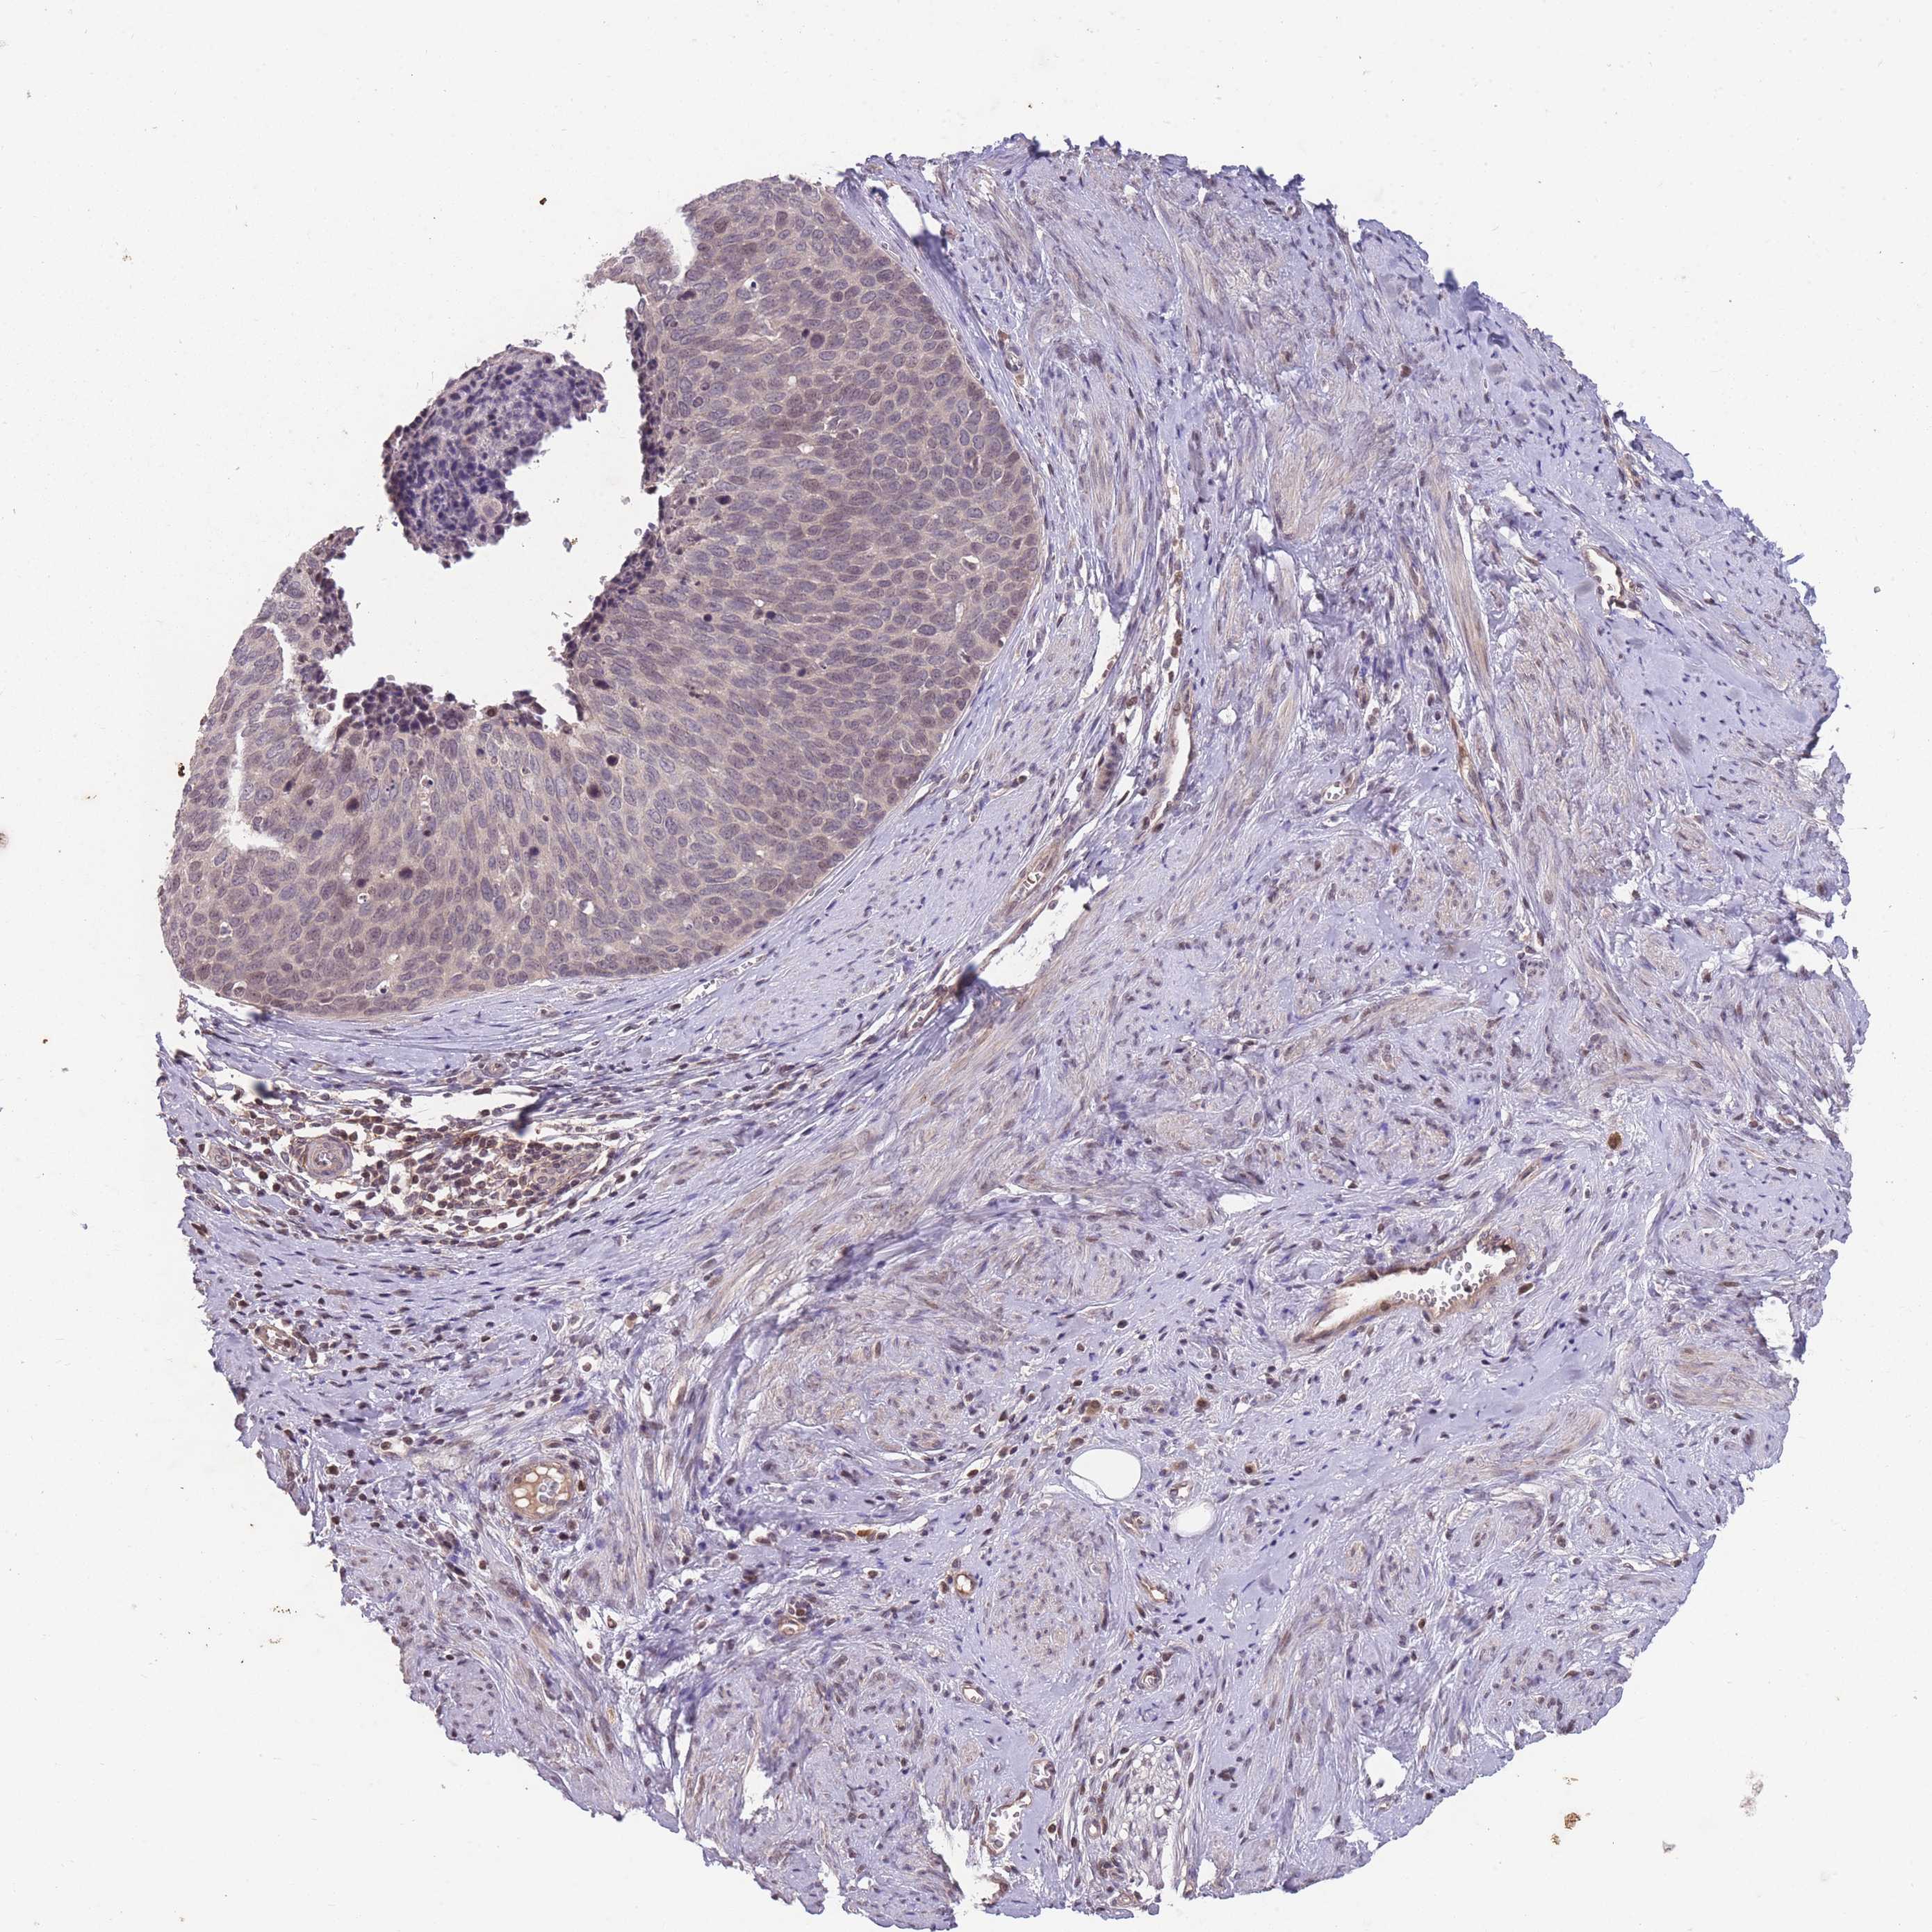

CERVICAL CANCER - Protein expressioni

A mouse-over function shows sample information and annotation data. Click on an image to view it in a full screen mode. Samples can be filtered based on level of antibody staining by selecting one or several of the following categories: high, medium, low and not detected. The assay and annotation is described here.

Note that samples used for immunohistochemistry by the Human Protein Atlas do not correspond to samples in the TCGA dataset.

Antibody stainingi

Antibody staining in the annotated cell types in the current human tissue is reported as not detected, low, medium, or high, based on conventional immunohistochemistry profiling in selected tissues. This score is based on the combination of the staining intensity and fraction of stained cells.

Each image is clickable and will lead to virtual microscopy that enables deeper exploration of all samples and also displays staining intensity scores, fraction scores and subcellular localization as well as patient and tissue information for each sample.

Antibody HPA008121

Antibody CAB032489

Squamous cell carcinoma, NOS

Adenocarcinoma, NOS